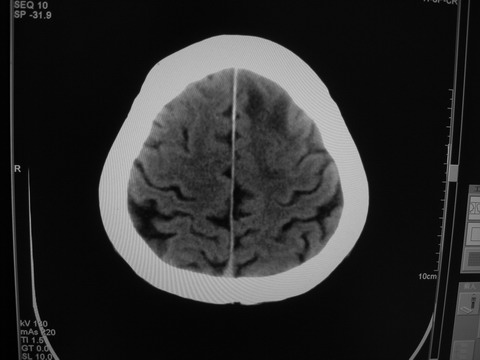

患者 男 69岁 头晕头痛不适

多发病灶,指状水肿,首先诊断转移瘤。

多个结节并周围大面积水肿区,多考虑多发性脑转移瘤

小病灶、大水肿,病灶多发,首先考虑多发转移瘤;建议查原发灶。

额顶叶多发小病灶、大水肿,首先考虑多发转移瘤;建议查原发灶

脑内多发病灶,小病灶,大水肿。

典型转移性肿瘤。

应进一步检查,查找原发病灶。

结果 : 该患者结肠癌病史5年 考虑脑转移

额叶结节病灶,不规则水肿范围大,加上年龄,首选转移